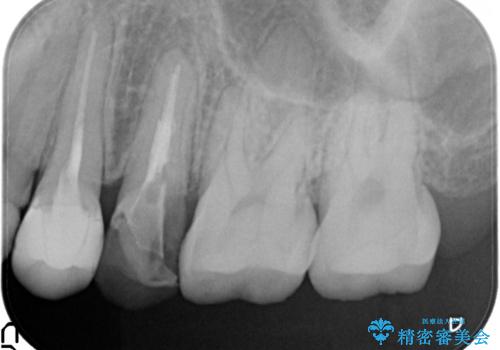

過去に治療してあった左上の歯が一部欠けていました。

かぶせ物と詰めてある修復物を除去すると歯肉の中まで虫歯になっていました。

歯を部分矯正で引き上げて、虫歯を徹底的に取り除き、適合の良いかぶせ物を装着する計画としました。